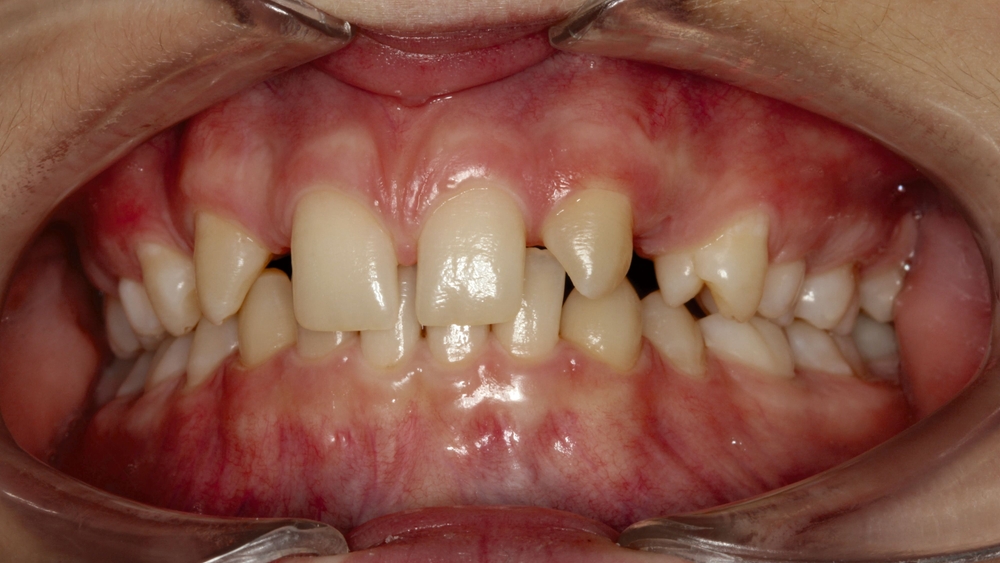

Bei dem gut zwölfjährigen Mädchen sind die seitlichen oberen Schneidezähne (Zähne 12 und 22) nicht angelegt. Zusätzlich zeigten sich verlagerte zweite obere Prämolaren.

Im vorliegenden Fall stand der Zahn 23 bereits im Mesialstand bei hoher Lachlinie und tendenziell konkavem Lippenprofil. Bezüglich Morphologie und Farbe waren die Zähne 13 und 23 nicht ausgeprägt eckzahntypisch. Es bestand kein Platzmangel im Gegenkiefer. Die Patientin war bei der Erstdiagnose 12,5 Jahre alt und im Wechselgebiss der zweiten Phase mit atypischer Durchbruchreihenfolge. Es bestand eine geringfügige Klasse II. Der Overjet war vergrößert bei vertikaler Wachstumstendenz, der Overbite war um circa einen Millimeter vergrößert aufgrund der geringfügigen Steilstellung der Oberkiefer-Front. Es bestand der Verdacht auf Nichtanlage der Weisheitszähne, 15 und 25 waren verlagert.